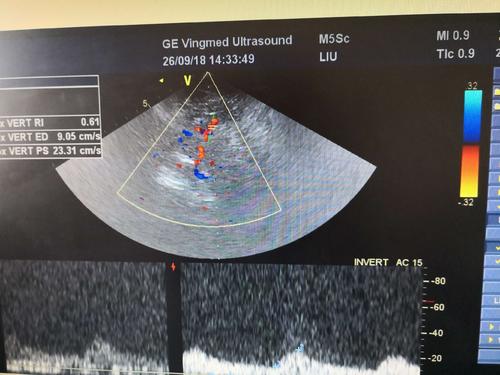

經顱彩色編碼雙功能超聲TCCD成像模式分析

TCCD成像模式

(1)依據(jù)多普勒頻移值編碼成像即f-TCCD:

依賴運動紅細胞所產生的多普勒頻移值進行計算機編碼,可以顯示血流方向和測算血流速度,需要校正多普勒取樣角度,角度及篩查深度依賴性較大,較易產生運動偽像。

(2)依據(jù)運動紅細胞所產生的總能量進行編碼成像即p-TCCD:

只與運動紅細胞所產生的總能量有關,無需校正多普勒取樣角度,對于受取樣角度影響較大血管病變,諸如大腦后動脈(PCA),大腦中動脈(MCA)M2段,大腦前動脈(ACA)A1段有一定的幫助作用,信噪比更高,不易產生混疊效應。p-TCCD相對f-TCCD而言,缺點是不能顯示血流方向,對顯示狹窄處高速血流敏感性較低。